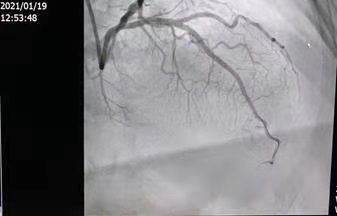

来自渭南市临渭区的患者杨某是首位获益者。患者杨某,80岁,以“胸部憋闷不适一周余”来渭南市第一医院心脏中心就诊,经心电图及抽血等检查后,显示为“急性下壁心肌梗死”,行造影检查结果显示:前降至与对角支分叉处及中段血管狭窄严重,右冠近中段严重狭窄。

图为患者三支血管病变,保守治疗风险较高,要分次手术,与家属充分沟通后行支架植入手术

在唐都医院张东伟教授团队充分的术前准备、精准操作下,在科室负责人梁兴盛医师、谢军芳副主任医师、王伟副主任医师介入团队的共同协作下,使用“crush”双支架技术,成功为患者实施了前降支与对角支分叉处支架植入手术,术后造影结果显示,患者堵塞的血管血流通畅,患者胸痛症状缓解。